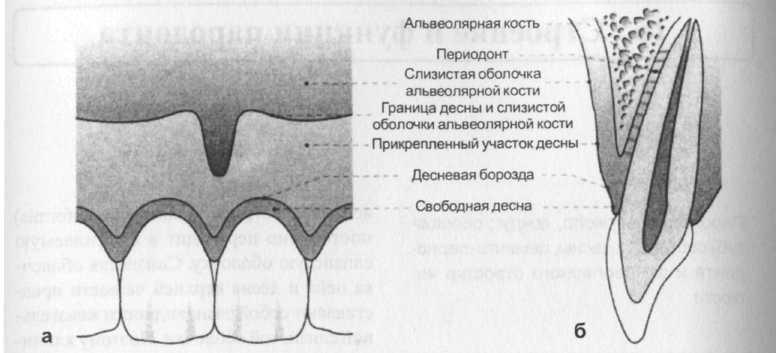

Анатомия: Межкорневая костная перегородка